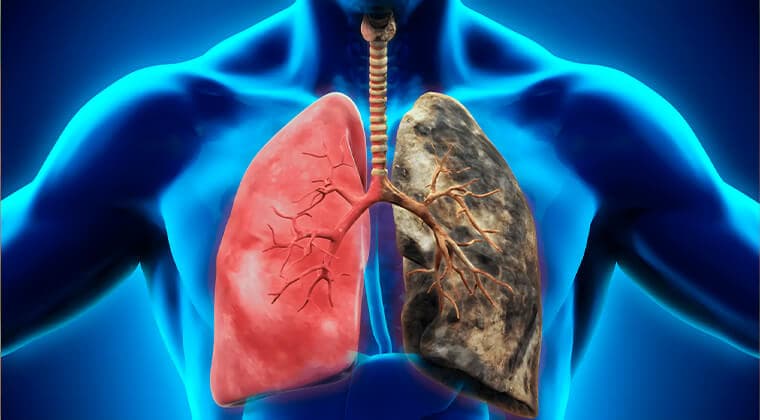

Fibrosis pulmonar

Endurecimiento y cicatrización de los pulmones que provoca falta de aire progresiva.